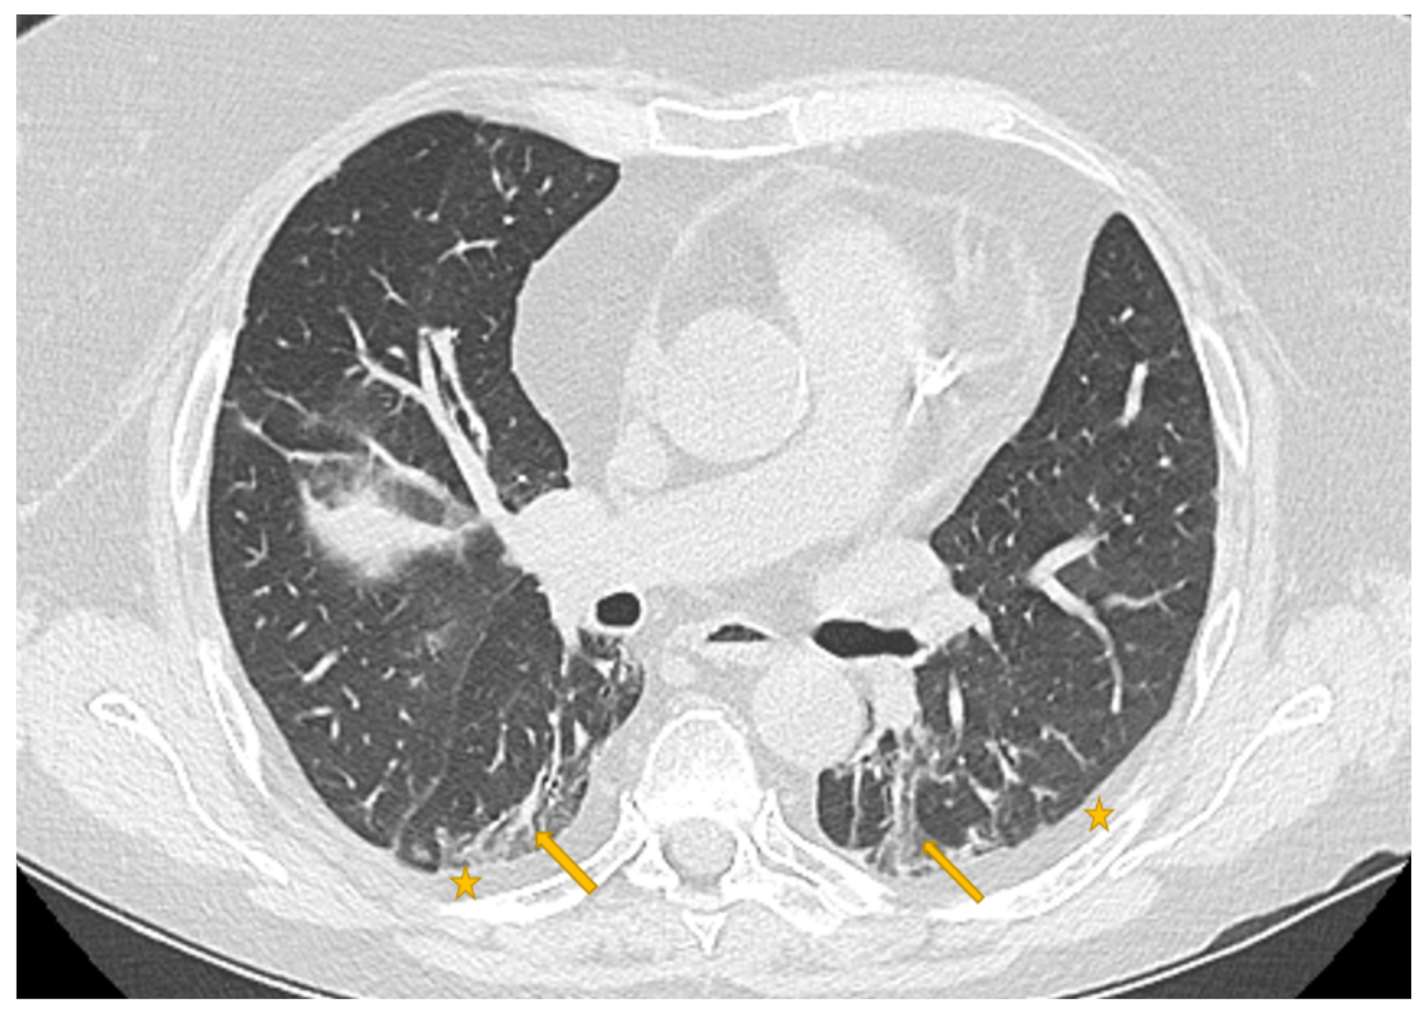

Every medical image is a combination of grey-levels that produce the morphology of the image. In this specific case, the attention is focused on HRCT images of the lung. In particular, the external part of a healthy lung would be white, while the inner part of the lung would be black. In this black part there could be different movements that display normal respiration and the performance of vital functions. Through these images, in the black section of the lung, radiologists can note some white spots that can be marked as disease symptoms, but they would not know to which disease the marks refer. For example, in Figure 5, Figure 6 and Figure 7 there are three different HRCT belonging to three different patients: one image has ”very black” lungs, while the others have some white spots. As a matter of fact, the Figure 5 is an HRCT of a healthy patient and it does not show white spots or pneumonia signs. The Figure 6 and Figure 7 are similar, because they both show some disease marks: the first is from a COVID-19 patient, while the second is from a lung disease patient. Thanks to this, it is clear just how difficult it is to see the differences between a general pneumonia and Coronavirus disease with the naked eye.

Figure 7. HRCT scan of a lung pneumonia. The imaging revealed lesions in the form of multiple confluent patchy areas of ground glass opacities seen scattered at both lungs (yellow arrows)—peripheral in distribution and bilateral minimal pleural effusion (yellow stars).